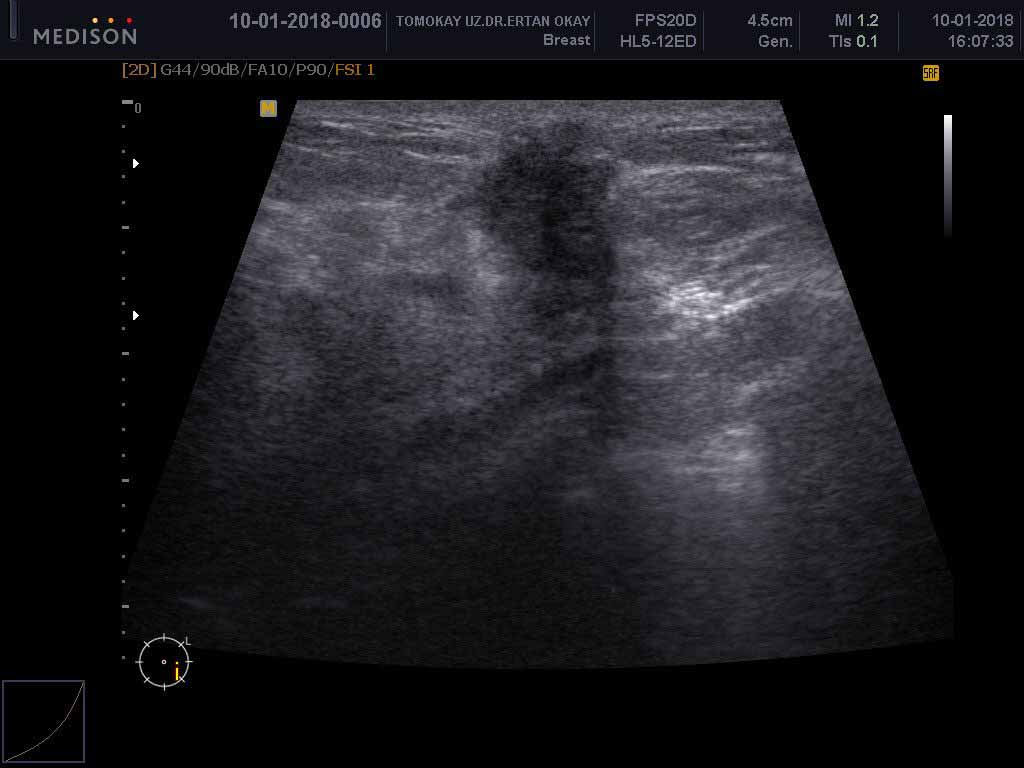

الموجات فوق الصوتية للثدي